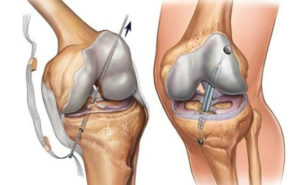

Выполняют 2 вида операций по восстановлению связок коленного сустава: артротомию – вскрытие сустава, хирургическую артроскопию – через аппарат артроскоп.

Артроскопическая операция

Кроме аппарата артроскопа в сустав вводят специальные тонкие инструменты через небольшие дополнительные надрезы. Удаляют разволокненную связку и заменяют ее имплантом, введенным через просвет артроскопа. Более современная технология – лазерная пластика.

Операция соединения ПКС называется пластикой. Основной метод, посредством которого она проводится, — артроскопия. При этом не требуется делать надрезы, достаточно небольших проколов кожных покровов. Используется артроскоп — это прибор, оснащенный видеокамерой.

Благодаря ему выполняется внутренний осмотр сустава, если имеет место разрыв крестообразных связок. Изображение передается на монитор со значительным увеличением. Для введения инструмента делают еще один прокол кожных покровов.

Так выполняется операция по восстановлению функциональности связок.

Лечение предусматривает операцию по фиксации крестообразной связки. В основном используется артроскопия. Она производится так:

- Для начала производится диагностика разрыва.

- Далее, необходимо взять трансплантат из других связок пациента или же подобрать искусственный эндопротез.

- Теперь специалисты должны сформировать бедренный туннель. Он делается в месте крепления крестообразной связки.

- Фиксация трансплантата в проделанных ранее каналах при помощи металлических крепежей или винтов.

Для операции используются связки надколенника, трупный материал, подколенные сухожилия или искусственные трансплантаты. После операции необходимо пройти курс восстановления.